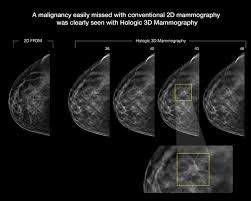

Most screening mammograms include two views of each breast taken from different angles. Abnormalities such as cancerous tumors usually appear brighter because they are denser. Any area that does not look like normal tissue is a possible cause for concern. However, 3d allows us to 'slice through' the breast, making thin sections, like on a ct scan. A diagnostic mammogram is used to check for breast cancer when there is a sign or symptom of disease. These deposits show up as tiny white spots on a mammogram, and there may be only one or two, or too many to count, says jay baker, md, a breast imaging specialist at the duke cancer center. 1 the gray areas correspond to normal fatty tissue, while the white areas are normal breast tissue with ducts and lobes. A 3d mammogram is used to look for breast cancer in people who have no signs or symptoms. Screening mammograms have been used since the 1980s. Dense breast tissue appears solid. Digital breast tomosynthesis (tomo), also known as 3d mammography, is a revolutionary new screening and diagnostic breast imaging tool to improve the early detection of breast cancer. Moose & doc breast cancer, 21 may 2018. Calcifications are calcium deposits within the breast tissue and they look like small white spots.

Diagnosis And Staging Of Breast Cancer When And How To Use Mammography Tomosynthesis Ultrasound Contrast Enhanced Mammography And Magnetic Resonance Imaging Springerlink from media.springernature.com What does breast cancer look like on a mammogram? More importantly, the overlap can obscure small breast cancers. Tumors may be benign or cancerous. A number of studies have found that 3d mammograms find more cancers than traditional 2d mammograms and also reduce the number of false positives. What does breast cancer look like on a mammogram? Images are displayed as a series of thin slices that can. Digital breast tomosynthesis (tomo), also known as 3d mammography, is a revolutionary new screening and diagnostic breast imaging tool to improve the early detection of breast cancer. The doctor reading your mammogram will be looking for different types of breast changes, such as small white spots called calcifications, larger abnormal areas called masses, and other suspicious areas that could be signs of cancer.

Most people assume that what doctors are looking for on a mammogram are lumps, dr. Diagnostic mammograms involve taking more views than screening mammograms. This decreases the overlap and makes it easier to see cancers. additionally, the combination of 2d and 3d mammogram imaging has been shown to reduce false positives that require a patient to return to the clinic for additional screening. Suspicious findings include clusters of tiny microcalcifications or a density/mass with irregular or spiculated margins. Most screening mammograms include two views of each breast taken from different angles. American cancer society, 9 oct 2017. A screening mammogram is performed at regular intervals to check for breast cancer in women who have no signs or symptoms of the disease. Images are displayed as a series of thin slices that can. A tumor that is benign, it is not a health problem and it may not grow or change shape. Several patterns of calcifications are seen with dcis, including: Even if you have a lump in only one breast, pictures will be taken of both breasts. A lump or tumor will show up as a focused white area on a mammogram. That makes it easy to detect abnormalities, which generally show up as white.

Mammogram Images Normal Abnormal And Breast Cancer from cdn-prod.medicalnewstoday.com The doctor reading your mammogram will be looking for different types of breast changes, such as small white spots called calcifications, larger abnormal areas called masses, and other suspicious areas that could be signs of cancer. What does breast cancer look like? That makes it easy to detect abnormalities, which generally show up as white. Normal breast tissue can look 100,000 different ways on a mammogram. This decreases the overlap and makes it easier to see cancers. additionally, the combination of 2d and 3d mammogram imaging has been shown to reduce false positives that require a patient to return to the clinic for additional screening. Bright spots on a mammogram that look like potential tumors could turn out to be overlapping tissues or a blood vessel folding over on itself, friedewald said. 1 the gray areas correspond to normal fatty tissue, while the white areas are normal breast tissue with ducts and lobes. This overlapping tissue can cause the resulting image to look like cancer.